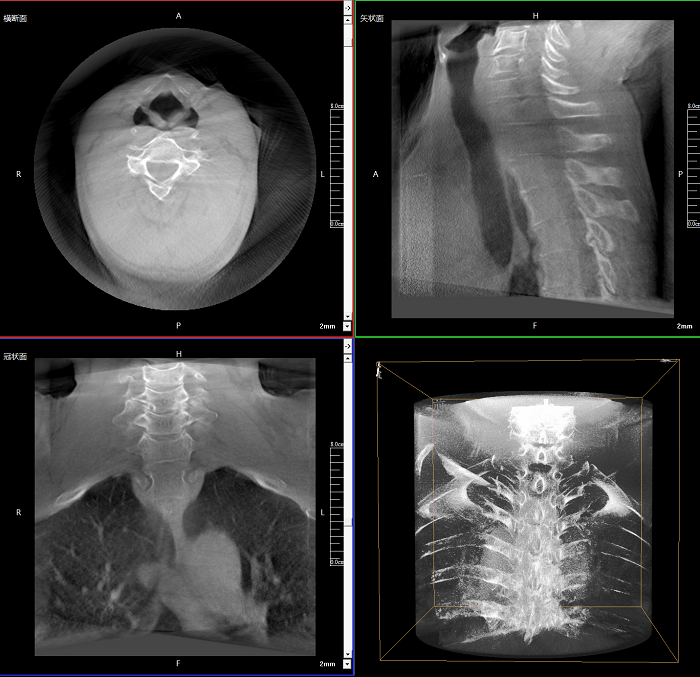

該設(shè)備可進(jìn)行快速的術(shù)中三維掃描,生成類CT斷層圖像和立體3D圖像,保障植入物置入效果。廣泛適用于骨科、脊柱外科、矯形外科、創(chuàng)傷骨科等其他領(lǐng)域。

術(shù)中實(shí)時(shí)生成橫斷面、矢狀面、冠狀面及三維影像,可在任意切面、任意角度評估植入物和解剖結(jié)構(gòu)的相對位置。

較9英寸常規(guī)平板視野提升100%,幫助醫(yī)生迅速判斷椎體節(jié)段,定位手術(shù)部位。

400萬像素成像

易于觀察細(xì)微病灶,利于胸部、腹部、脊柱關(guān)節(jié)等復(fù)雜骨骼和軟組織的成像。

Clinical picture

臨床圖片